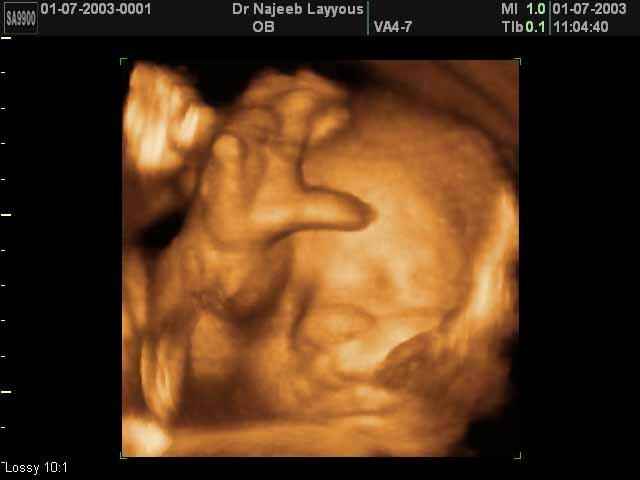

- صور لوجه الجنين في داخل الرحم

- صور جانبية لرأس الجنين

- تصرفات الجنين داخل الرحم

- أهمية التصوير بالموجات فوق الصوتية رباعي الابعاد في الحمل 4D ultrasound

صور لوجه الجنين بجهاز الالتراساوند ثلاثي الأبعاد | الدكتور نجيب ليوس